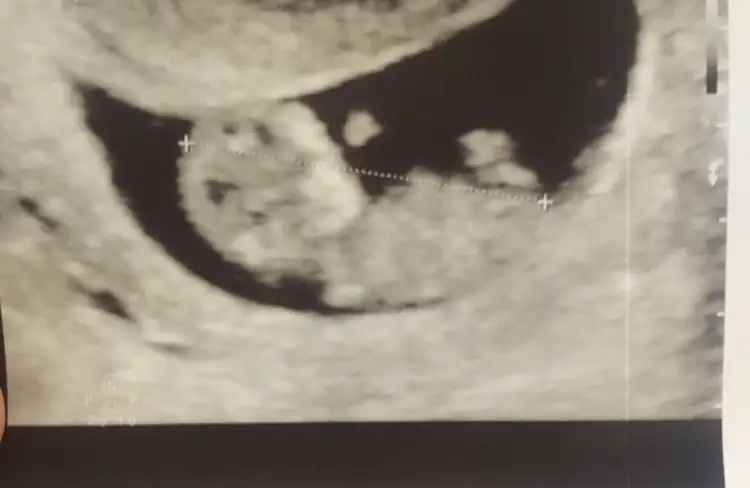

Bana da bakarmisiniz lutfen 🙏🙏

Benim 6+4 de bi sag da bi solda gorundu..

7+6 goruntude ortada gorundu... hepsi de karından 🙏